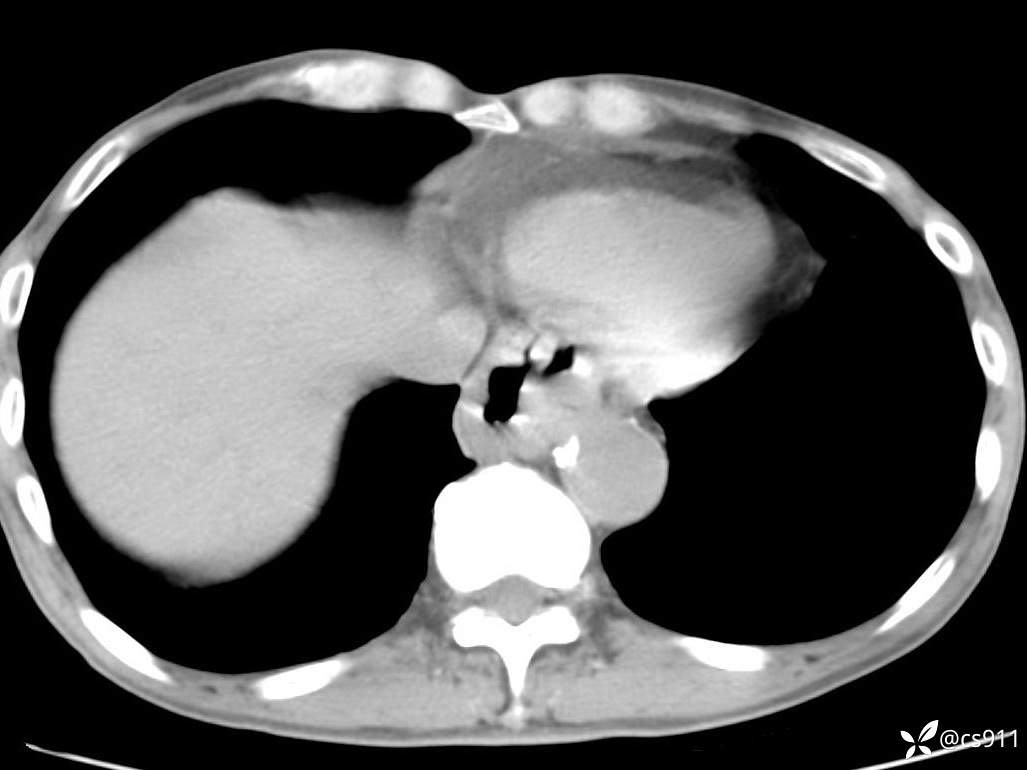

急腹症之急诊CT,原因?答案公布

男,77岁,腹痛、腹胀伴恶心呕吐1天。呕吐胃内容物,非喷射性呕吐,有咖啡色样胃内容物,诉有胃穿孔病史。查体:全腹平,下腹部压痛,全腹无反跳痛,叩诊呈浊音,移动性浊音阴性,肠鸣音减弱,1-2次/分。肛检:直肠未扪及明显肿物,可触及大量粪块。

血淀粉酶(AMY) HH 1859 U/L 35-135

癌胚抗原(CEA) H 27.44 ng/ml 0-5